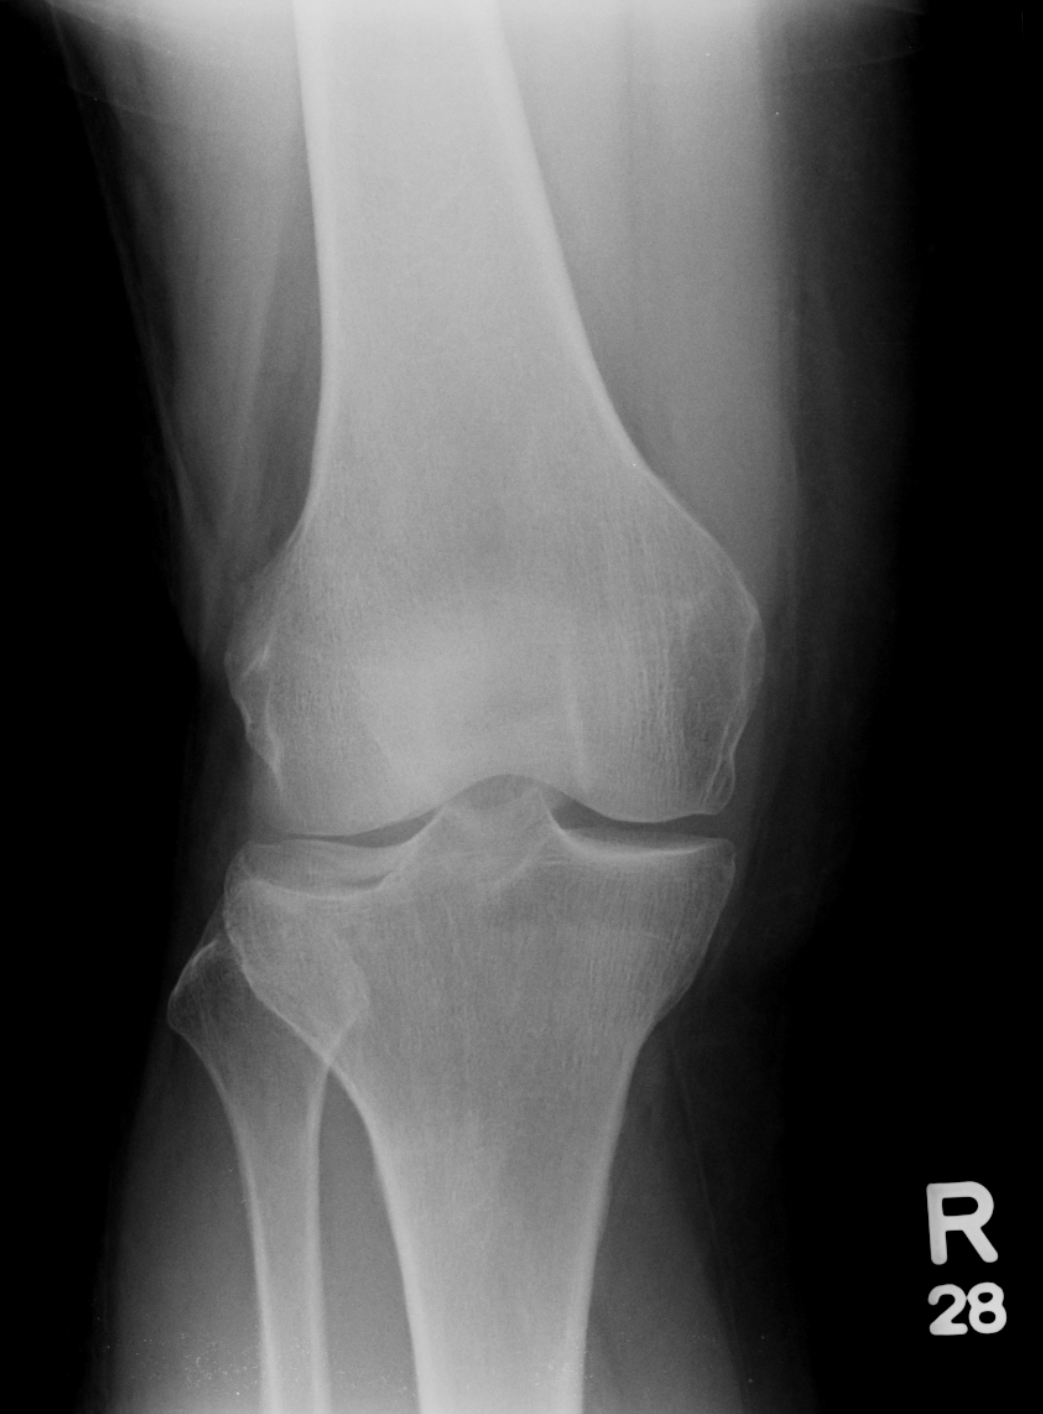

Knee normal ap. This is the insall salvatti ratio and should ideally me measure with the knee flexed at 30 degrees.

Ap stands for anteroposterior meaning the image is directed from the front to the back of the knee joint.

In the context of trauma the lateral view is acquired with the patient lying supine and with a horizontal x ray beam. Knee x rays are done to assess the knee joint pathology. This is a front to back view of the knee joint also called the ap view.

The knee joint is a modified hinge joint between the femur tibia and patella. Check for errors and try again. Normal radiographic anatomy of the knee.